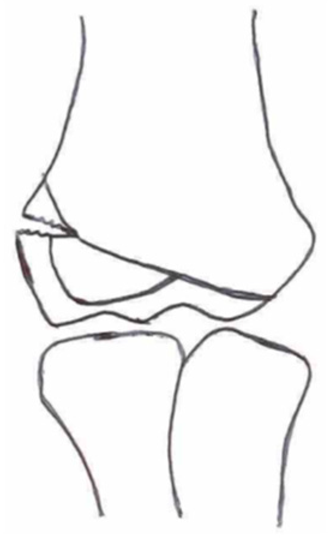

2.3. Classification of Fractures

| Classification | Type 1 (A) | Type 2 (B) | Type 3 (C) | Type 4 | Type 5 |